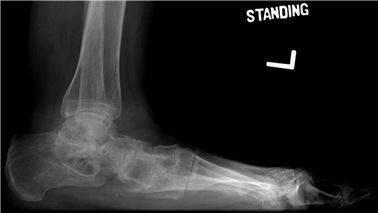

Weight-bearing anteroposterior (AP), lateral, and sesamoid axial radiographs are mandatory. On the AP view, the surgeon measures the Hallux Valgus Angle (HVA, normal < 15°), the Intermetatarsal Angle (IMA, normal < 9°), and the Distal Metatarsal Articular Angle (DMAA). The lateral view is scrutinized for Meary's angle (talo-first metatarsal angle) to identify midfoot collapse, as well as the presence of dorsal osteophytes indicative of hallux rigidus. The sesamoid axial view is critical for assessing the degree of sesamoid subluxation and the integrity of the crista.

Clinical & Radiographic Imaging Archive